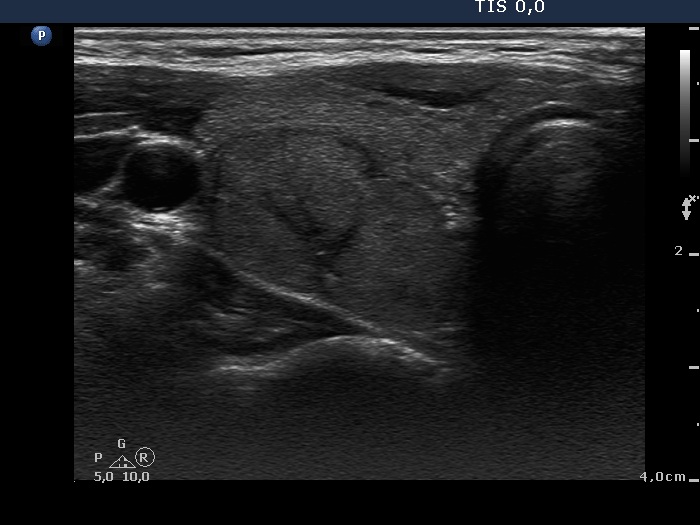

Ultrasonography. The thyroid was echonormal. There were several small, moderately hypoechogenic lesions and a larger, minimally hypoechogenic nodule in the right lobe. The latter was composed of smaller areas. The left thyroid contained moderately hypoechogenic small areas.